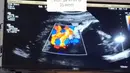

Hari-hari jelang melahirkan, Bebi memeriksakan kandungannya secara rutin. Dari hasil pemeriksaan USG, diketahui calon buah hatinya terlilit ari-ari. Sejak dua minggu lalu dan belum lepas. (Instagram/bebi.silvana)

"Tapi ada kabar yang tidak mengenakan yaitu lahiran harus dengan cara Cesar karena Bayi terlilit ari-ari 2x lilitan sejak 2 minggu lalu masih belum juga lepas," tulis bebi.silvana dalam unggahan 24 Juni. (Instagram/bebi.silvana)

Melihat kondisi janin yang terlilit ari-ari, untuk menghindari resiko pada janinnya, dokter menyarankan untuk melahirkan melalui operasi caesar. (Instagram/bebi.silvana)

"Aku Ingin Lahiran Normal dan ga mau ada riwayat Cesar dan saran dokter ini harus dilakukan Cesar karena beresiko bayi saat nanti dilahirkan tercekik karena tersangkut ari² di antara plasenta dan tali pusar yang terlilit di lehernya," lanjut Bebi. (Instagram/bebi.silvana)

Bebi yang kini hamil 35 minggu, masih berusaha untuk bisa melahirkan secara normal. Termasuk dengan cara-cara tradisional sesuai saran suami, orang tua, suudara dan juga teman-temannya. (Instagram/bebi.silvana)